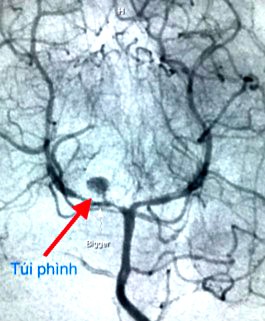

Nhận định trong trường hợp này, khả năng lớn là do vỡ túi phình mạch máu não. Do đó, bệnh nhi được tiến hành chụp mạch máu não xoá nền DSA để đánh giá cấu trúc mạch máu não, và kết quả cũng không nằm ngoài dự đoán. Bệnh nhi có túi phình ở động mạch não sau bên phải, và túi phình này bể ra gây nên tình trạng xuất huyết này.

Bệnh nhi được hội chẩn để lên phương án điều trị thích hợp. Do vị trí khó khăn, phẫu thuật khó tiếp cận, vì vậy can thiệp mạch được ưu tiên lựa chọn. Và đặt biệt, trong lần can thiệp nội mạch được tiến hành vài ngày sau khi khảo sát DSA, túi phình đã tăng kích thước hơn, và tiềm tàng nguy cơ tái vỡ, nếu không điều trị kịp thời. Những ống thông, dây dẫn siêu nhỏ được luồn vào mạch máu, tiếp cận được túi phình và tắc hoàn toàn túi phình bằng những vòng xoắn kim loại.